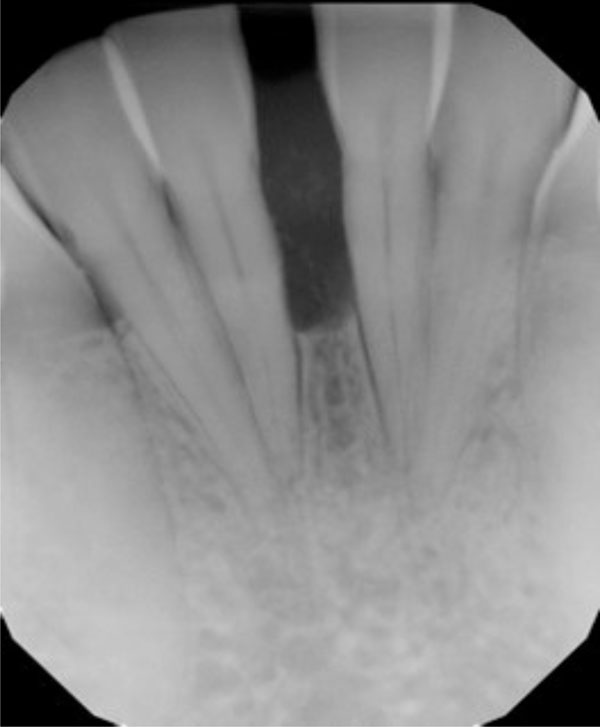

Fig. (3b).

Significant improvement in bone quantity and a reduction in the separation of teeth 24 and 25 are evident on the 6-month posttreatment radiograph.

The tumor was successfully removed, and to rebuild the hard and soft tissue that had been compromised as a result of tumor expansion, periodontal regenerative therapy was offered. The patient accepted the therapy and the surgical site was bone grafted, with excellent results (Figs. 3a and 3b). Preventive measures were taken before the tumor was able to spread further, which might have led to severe bone loss and possible complications.

Potential radiolucent lesions may include lateral periodontal cyst, central giant cell granuloma, ameloblastoma, or other odontogenic cysts. Therefore, biopsy was suggested to more precisely define the biological nature of the lesion. Surgical incisional biopsy was performed to diagnose the lesion, which was firm but asymptomatic and created a large diastema, widened the periodontal ligament, and led to divergent tooth roots over a 1-year period. Histological finding was COF, WHO type. The tumor was successfully removed, and periodontal regenerative therapy was performed to rebuild the hard and soft tissue that had been compromised as a result of tumor expansion. Preventive measures were taken before the tumor was able to spread further, which may have led to severe bone loss and possible complications. The site was grafted, with excellent results. The patient was satisfied with the outcome of treatment.